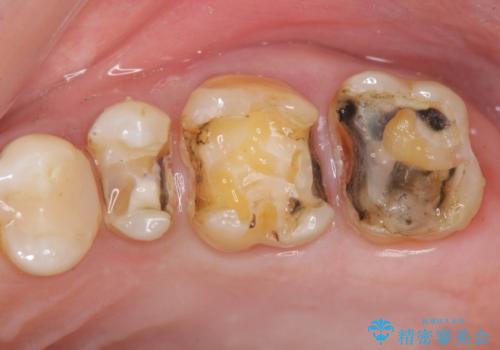

銀歯を丁寧に除去すると、銀歯の下で虫歯の再発やセメントの劣化が確認されたので、拡大鏡・マイクロスコープを用いて虫歯のみを丁寧に取り除いたのち、精密なセラミッククラウンの製作を進めます。

拡大鏡・マイクロスコープを用いて虫歯を丁寧に除去することで、健全な歯質や神経を守ることにつながります。